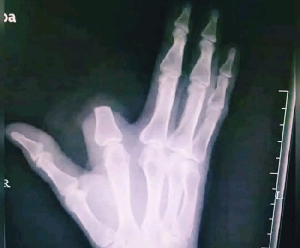

Le patient, dont les doigts de la main ont été passés au scanner, a bien été attaqué par le reptile. Comme tout le monde l’aurait fait, il a paniqué.

Dans la foulée, il s’est amputé un doigt dans une tentative désespérée d’arrêter la propagation du venin et de ne pas mourir. Il tient à la vie.

En conséquence, cette amputation radicale était totalement injustifiée. La victime s’est gratuitement débarrassée d’un de ses membres, mais il croyait faire le bon sacrifice.